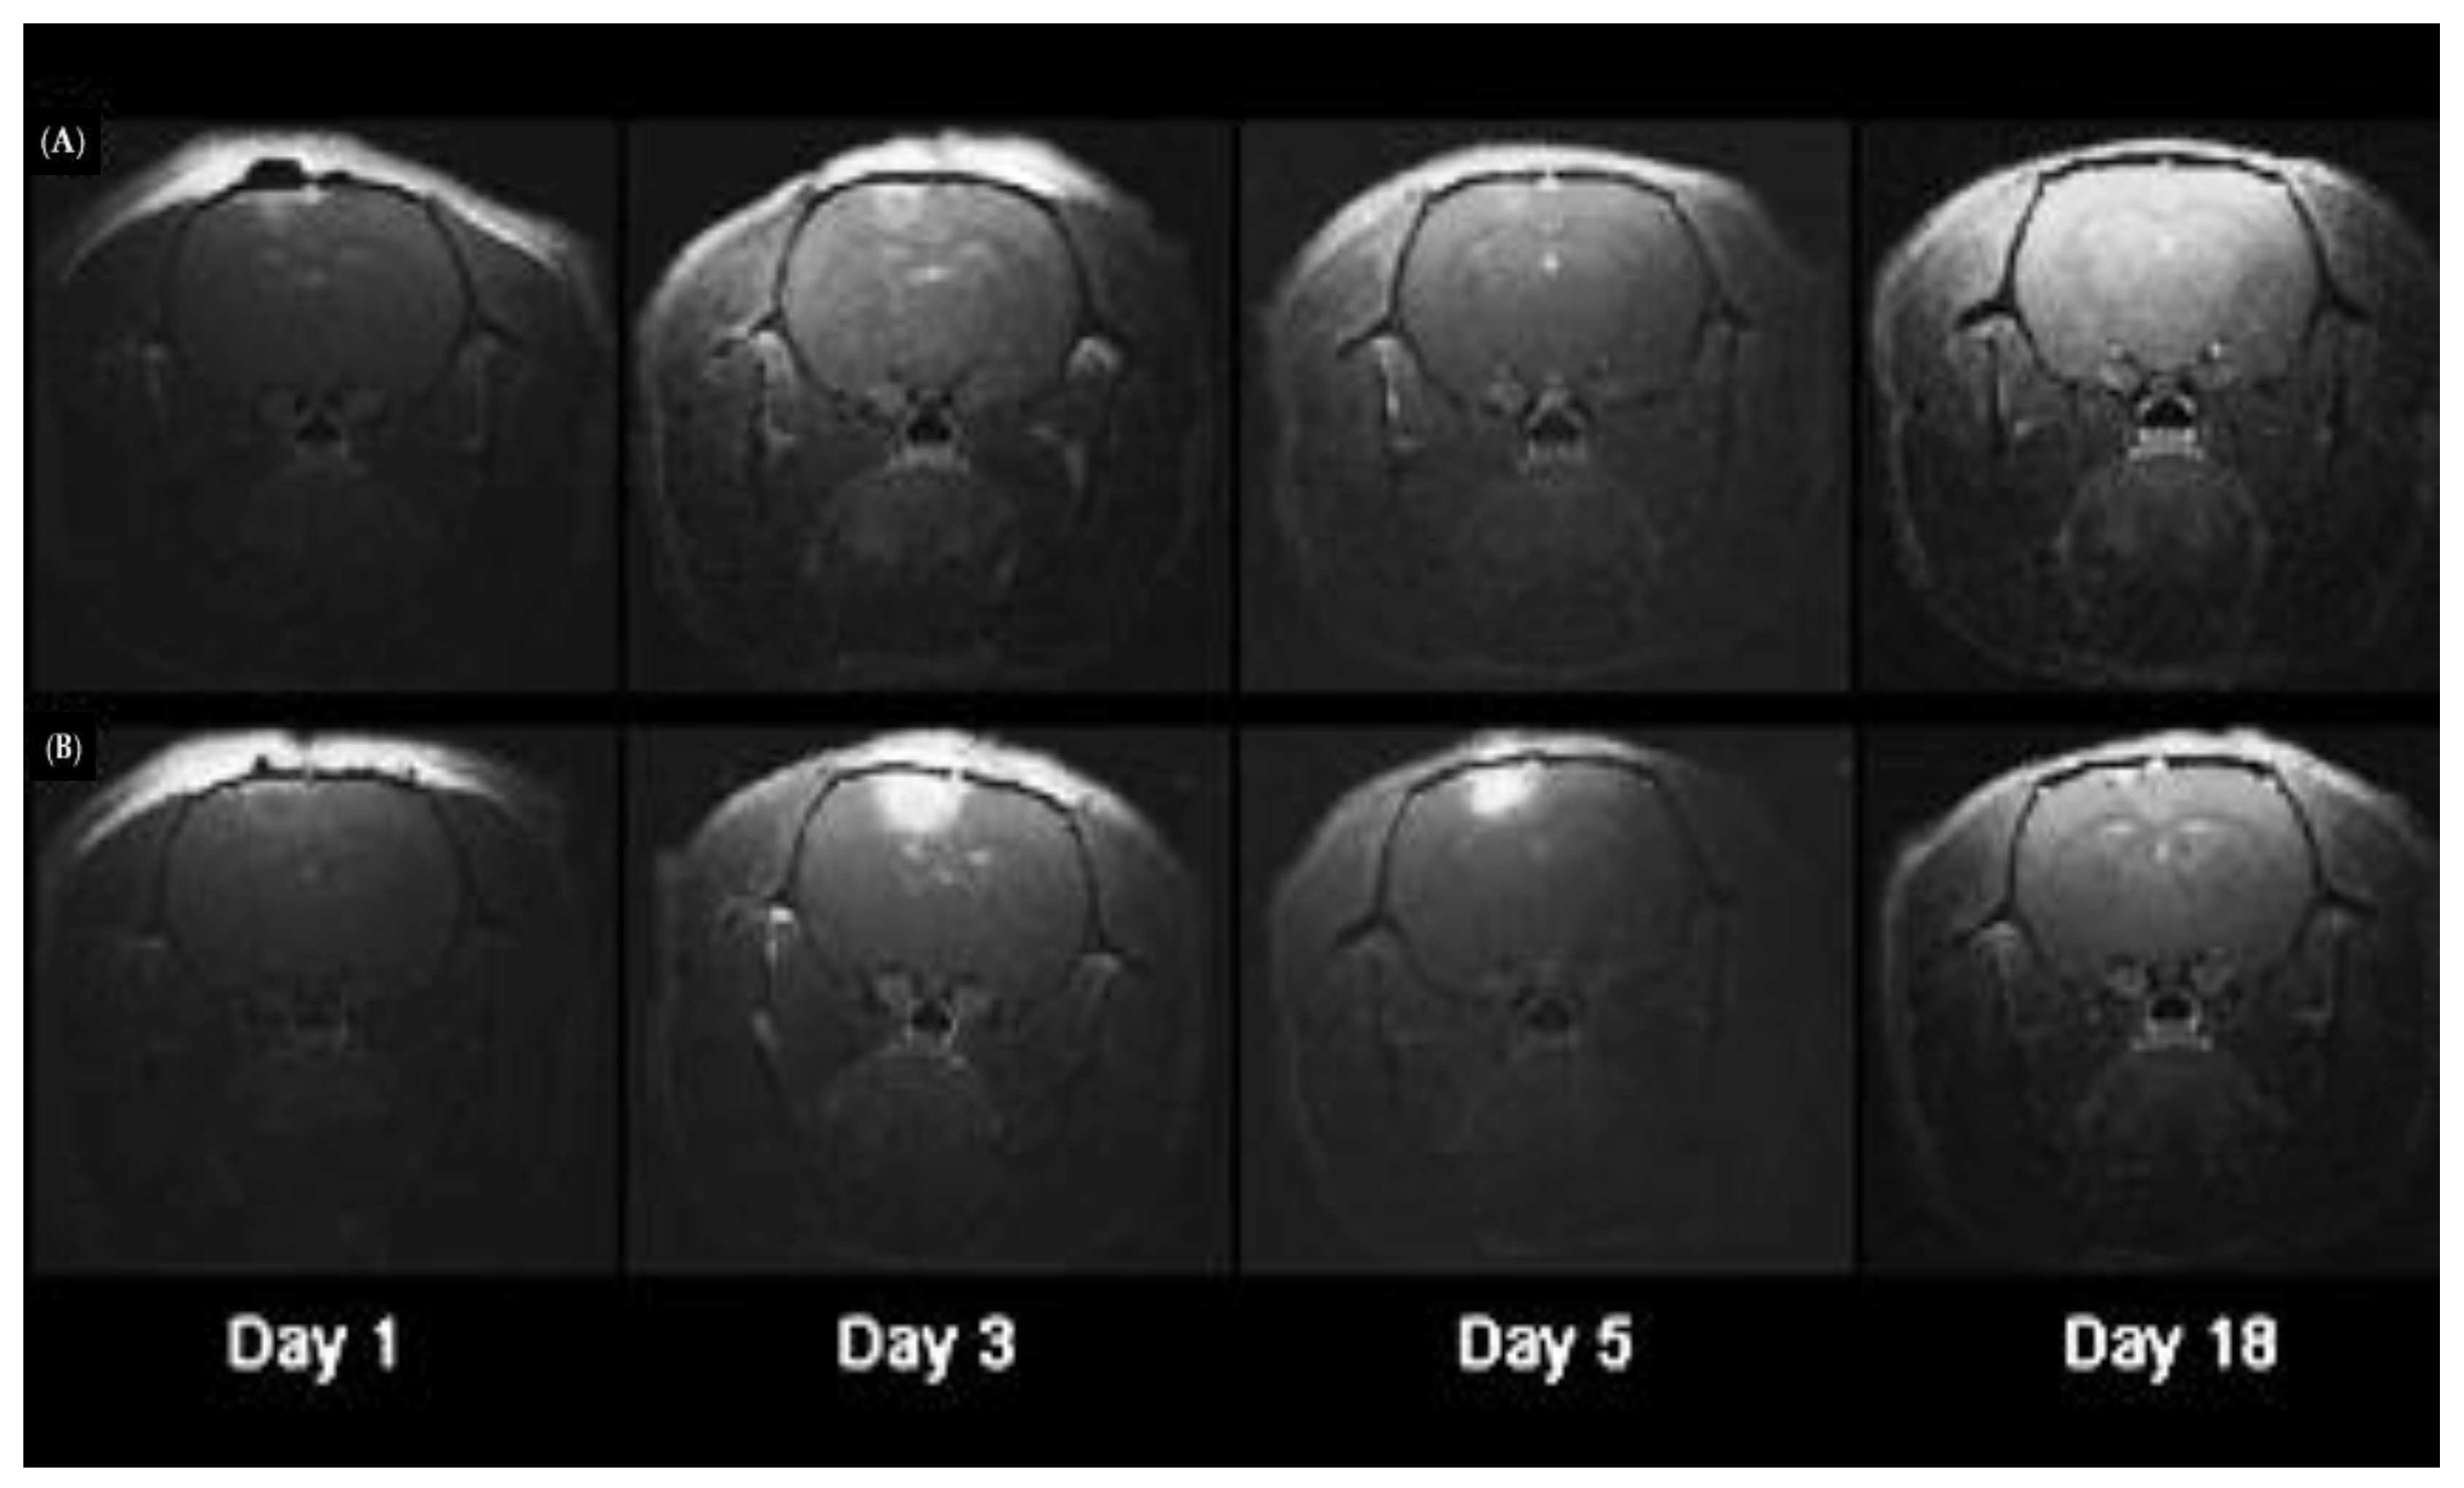

- Shin, D.; Christie, C.; Ju, D.; Nair, R.K.; Molina, S.; Berg, K.; Krasieva, T.B.; Madsen, S.J.; Hirschberg, H. Photochemical internalization enhanced macrophage delivered chemotherapy. Photodiagnosis Photodyn. Ther. 2018, 21, 156–162. [Google Scholar] [CrossRef] [PubMed]

- Shin, D.; Nguyen, L.; Le, M.T.; Ju, D.; Le, J.N.; Berg, K.; Hirschberg, H. The effects of low irradiance long duration photochemical internalization on glioma spheroids. Photodiagnosis Photodyn. Ther. 2019, 26, 442–447. [Google Scholar] [CrossRef]